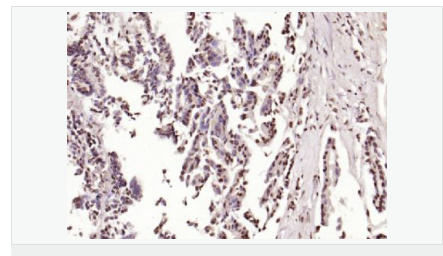

交叉反應(yīng):Human,Mouse,Rat(predicted:Dog,Pig,Rabbit,GuineaPig) 推薦應(yīng)用:IHC-P,IHC-F,ICC,IF,Flow-Cyt,ELISA

| 產(chǎn)品應(yīng)用 | ELISA=1:5000-10000 IHC-P=1:100-500 IHC-F=1:100-500 Flow-Cyt=1μg/Test ICC=1:100 IF=1:100-500 (石蠟切片需做抗原修復(fù)) not yet tested in other applications. optimal dilutions/concentrations should be determined by the end user. |